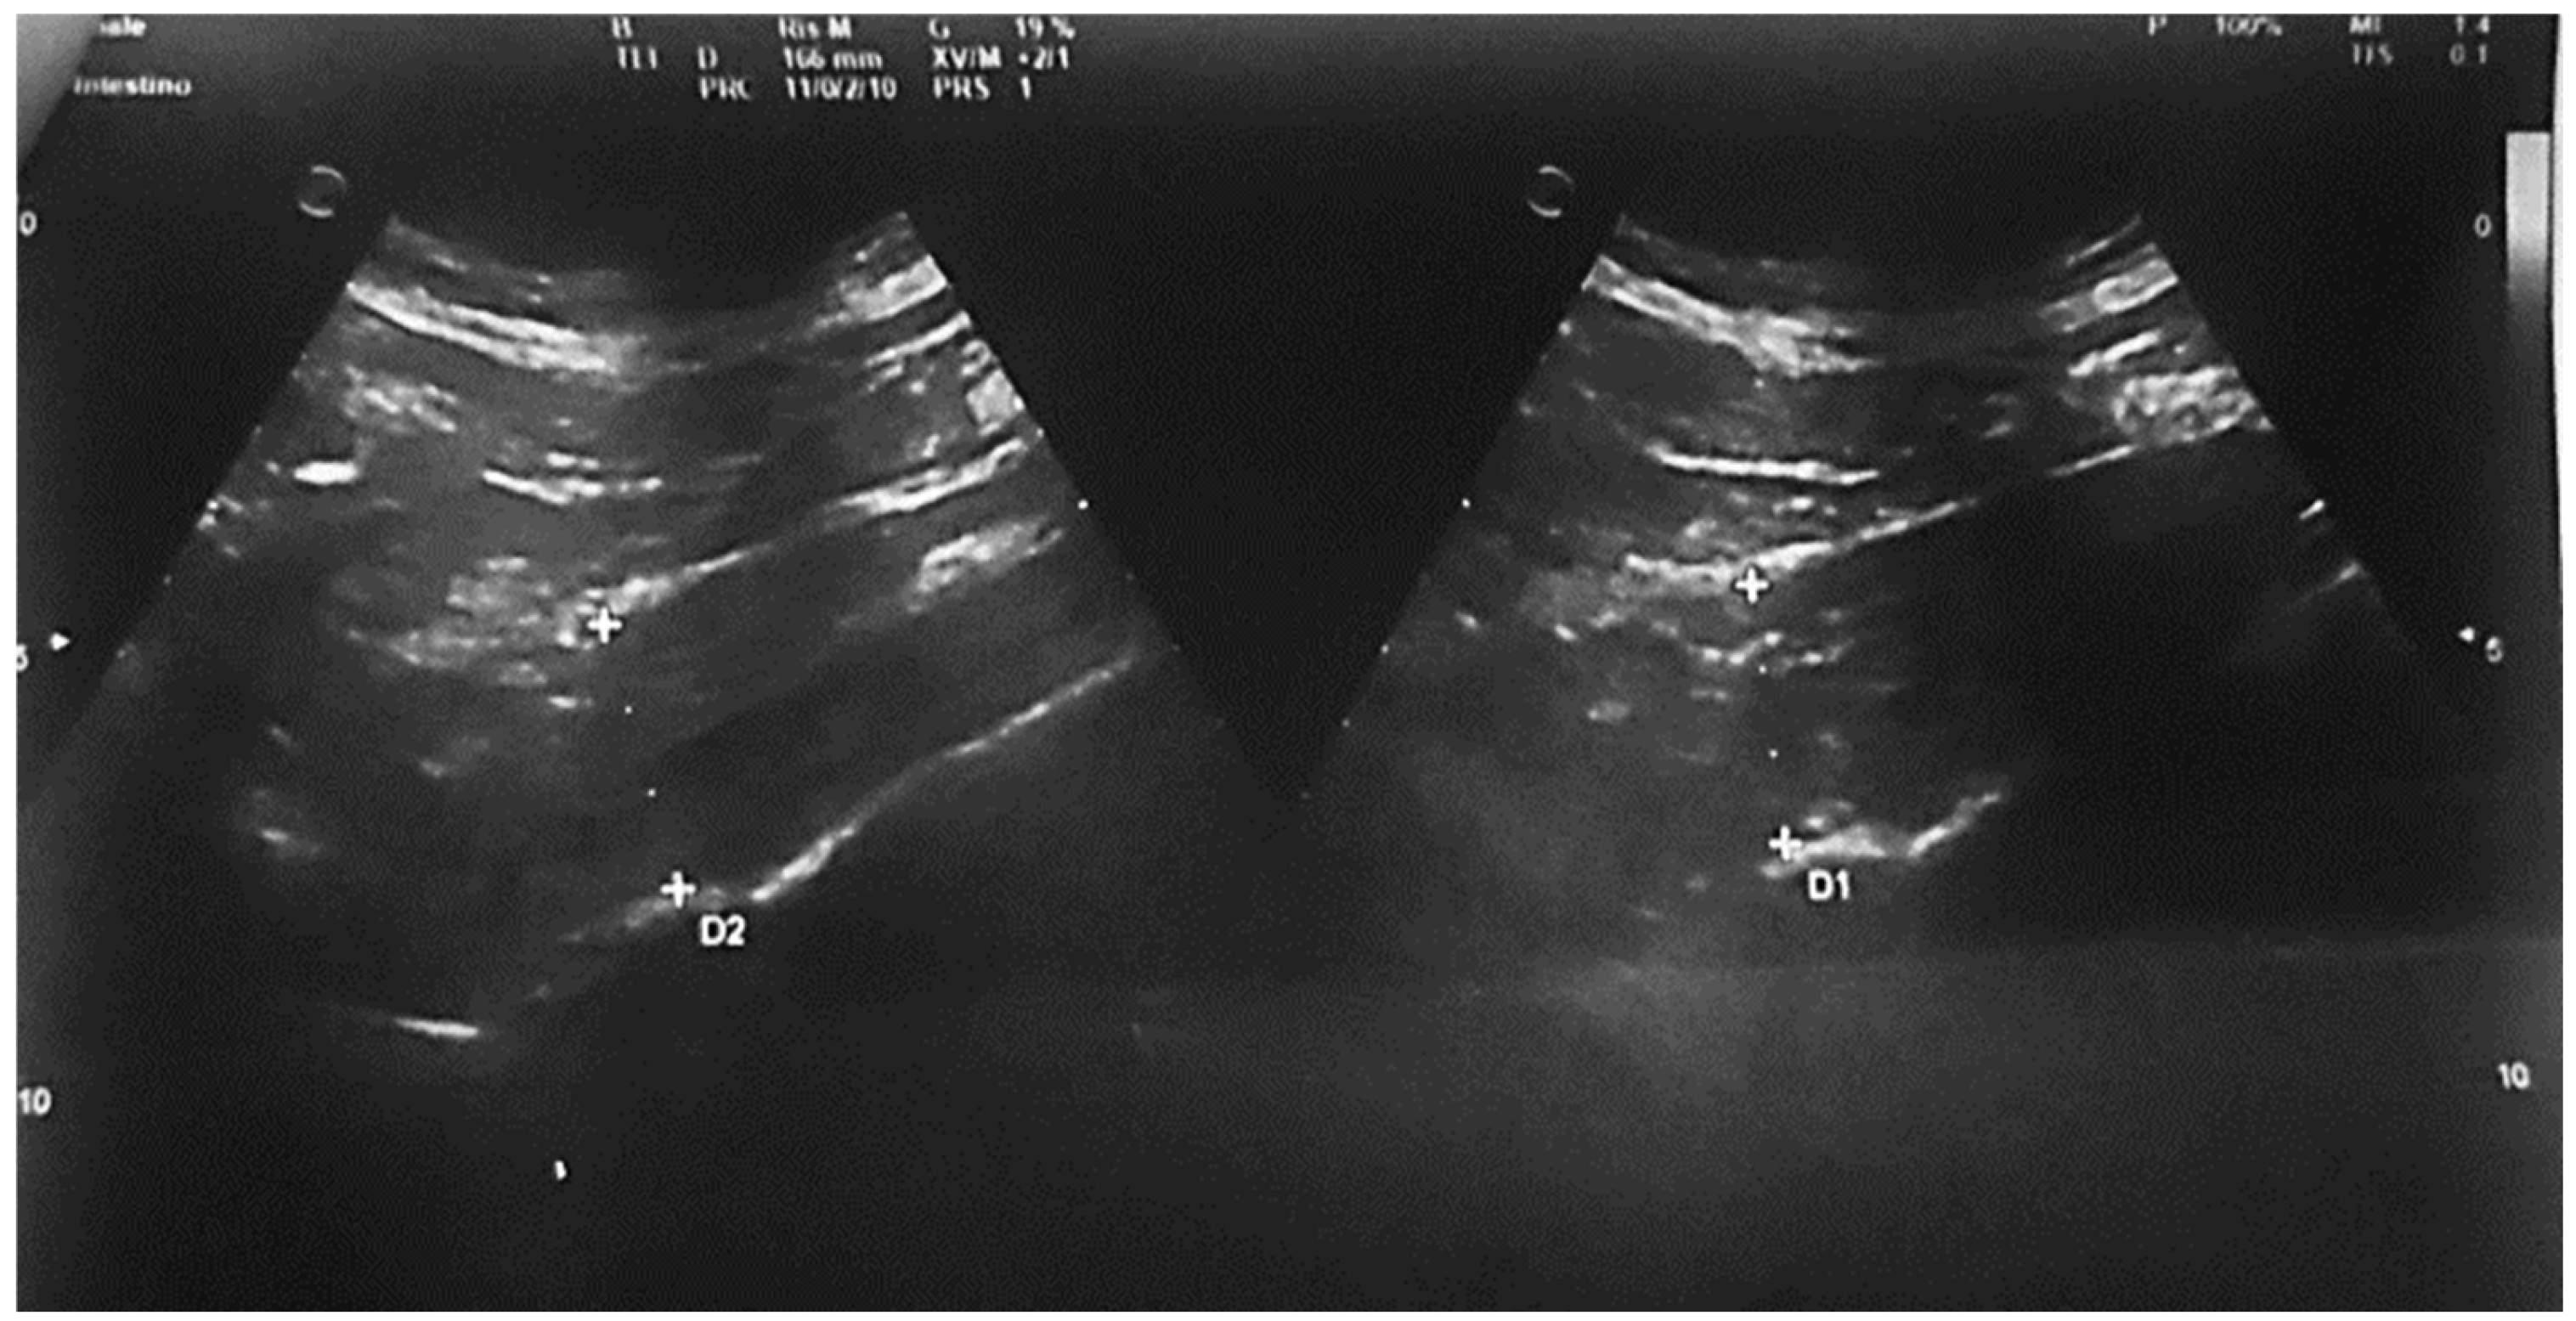

Psoas muscle (IP): the right psoas and adjacent lumbar vertebrae were identified. The abdominal probe was placed in a sagittal subphrenic position just above the iliac crest. The probe was slid anteromedially to poster laterally to identify the largest visible transverse diameter. Three measurements were taken, and their average was used. Measurements were considered “reliable” when: (a) all anatomical boundaries were clearly identified; and (b) no measurement deviated by >5 mm from the others. The psoas muscle thickness-to-height-ratio (PMTH) (mm/m) was then calculated (Figure 1).

Figure 1. Muscle US measurement. Right psoas muscle and concomitantly lying lumbar vertebrae were accurately recognized in each patient. Abdominal probe was positioned in a sagittal plane subphrenally right and just above the upper anatomical limit of the pelvis (iliac crest). Sliding the ultra-sonic probe in the anteromedial to posterolateral direction, the largest ultrasonically visible psoas muscle diameter was defined.